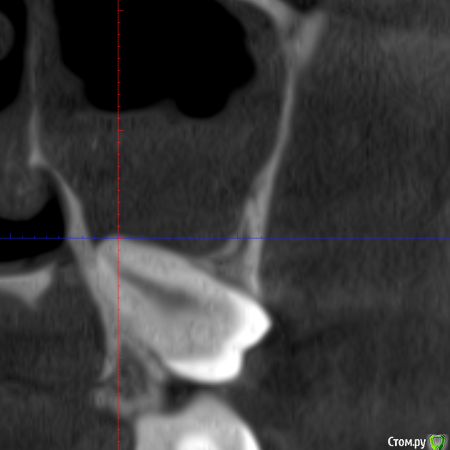

It'sGeorgy Опубликовано 11 декабря, 2019 Поделиться Опубликовано 11 декабря, 2019 (изменено) Всем здравствуйте! Слишком много проблемных пазух сыпется на меня в последнее время. Пациентку в лицо впервые увижу в пятницу, обратилась в клинику с жалобами "пол головы болит, сделайте что-то, мне в отпуск через месяц" . По телефонному разговору удалось разузнать: лежала в неврологии 3 месяца назад, где обострился гайморит. Там отправили к ЛОРами, те назначили антибиотики и сказали делать "кукушку", там же сделали КТ(в приложениях). После этого, пошла по ДМС к другому ЛОРу, показала КТ. Сказали, причина в восьмерке. Восьмерка полностью ретенирована(Со слов пациентки, опять же, сам не видел еще). Корень в пазухе(?). - прикрепленное 1.Рядом находится 2.7 с незапломбированным мб2 - прикрепленное 2. И недопломбированным небным корнем + воспаление на этом корне. - прикрепленное 3.Пазуха - прикрепленное 4. https://cloud.mail.ru/stock/bky4cB7brg4DmMjaY7NSGR7y - KT + MPT. Открывается винраром. На перелечивание 2.7 зуба пациентка может не согласиться. Удалять ли 2.7 зуб? Может ли ТОЛЬКО полностью ретинированная восьмерка вызвать подобное состояние пазухи или искать что-то еще? Изменено 11 декабря, 2019 пользователем It'sGeorgy Ссылка на комментарий